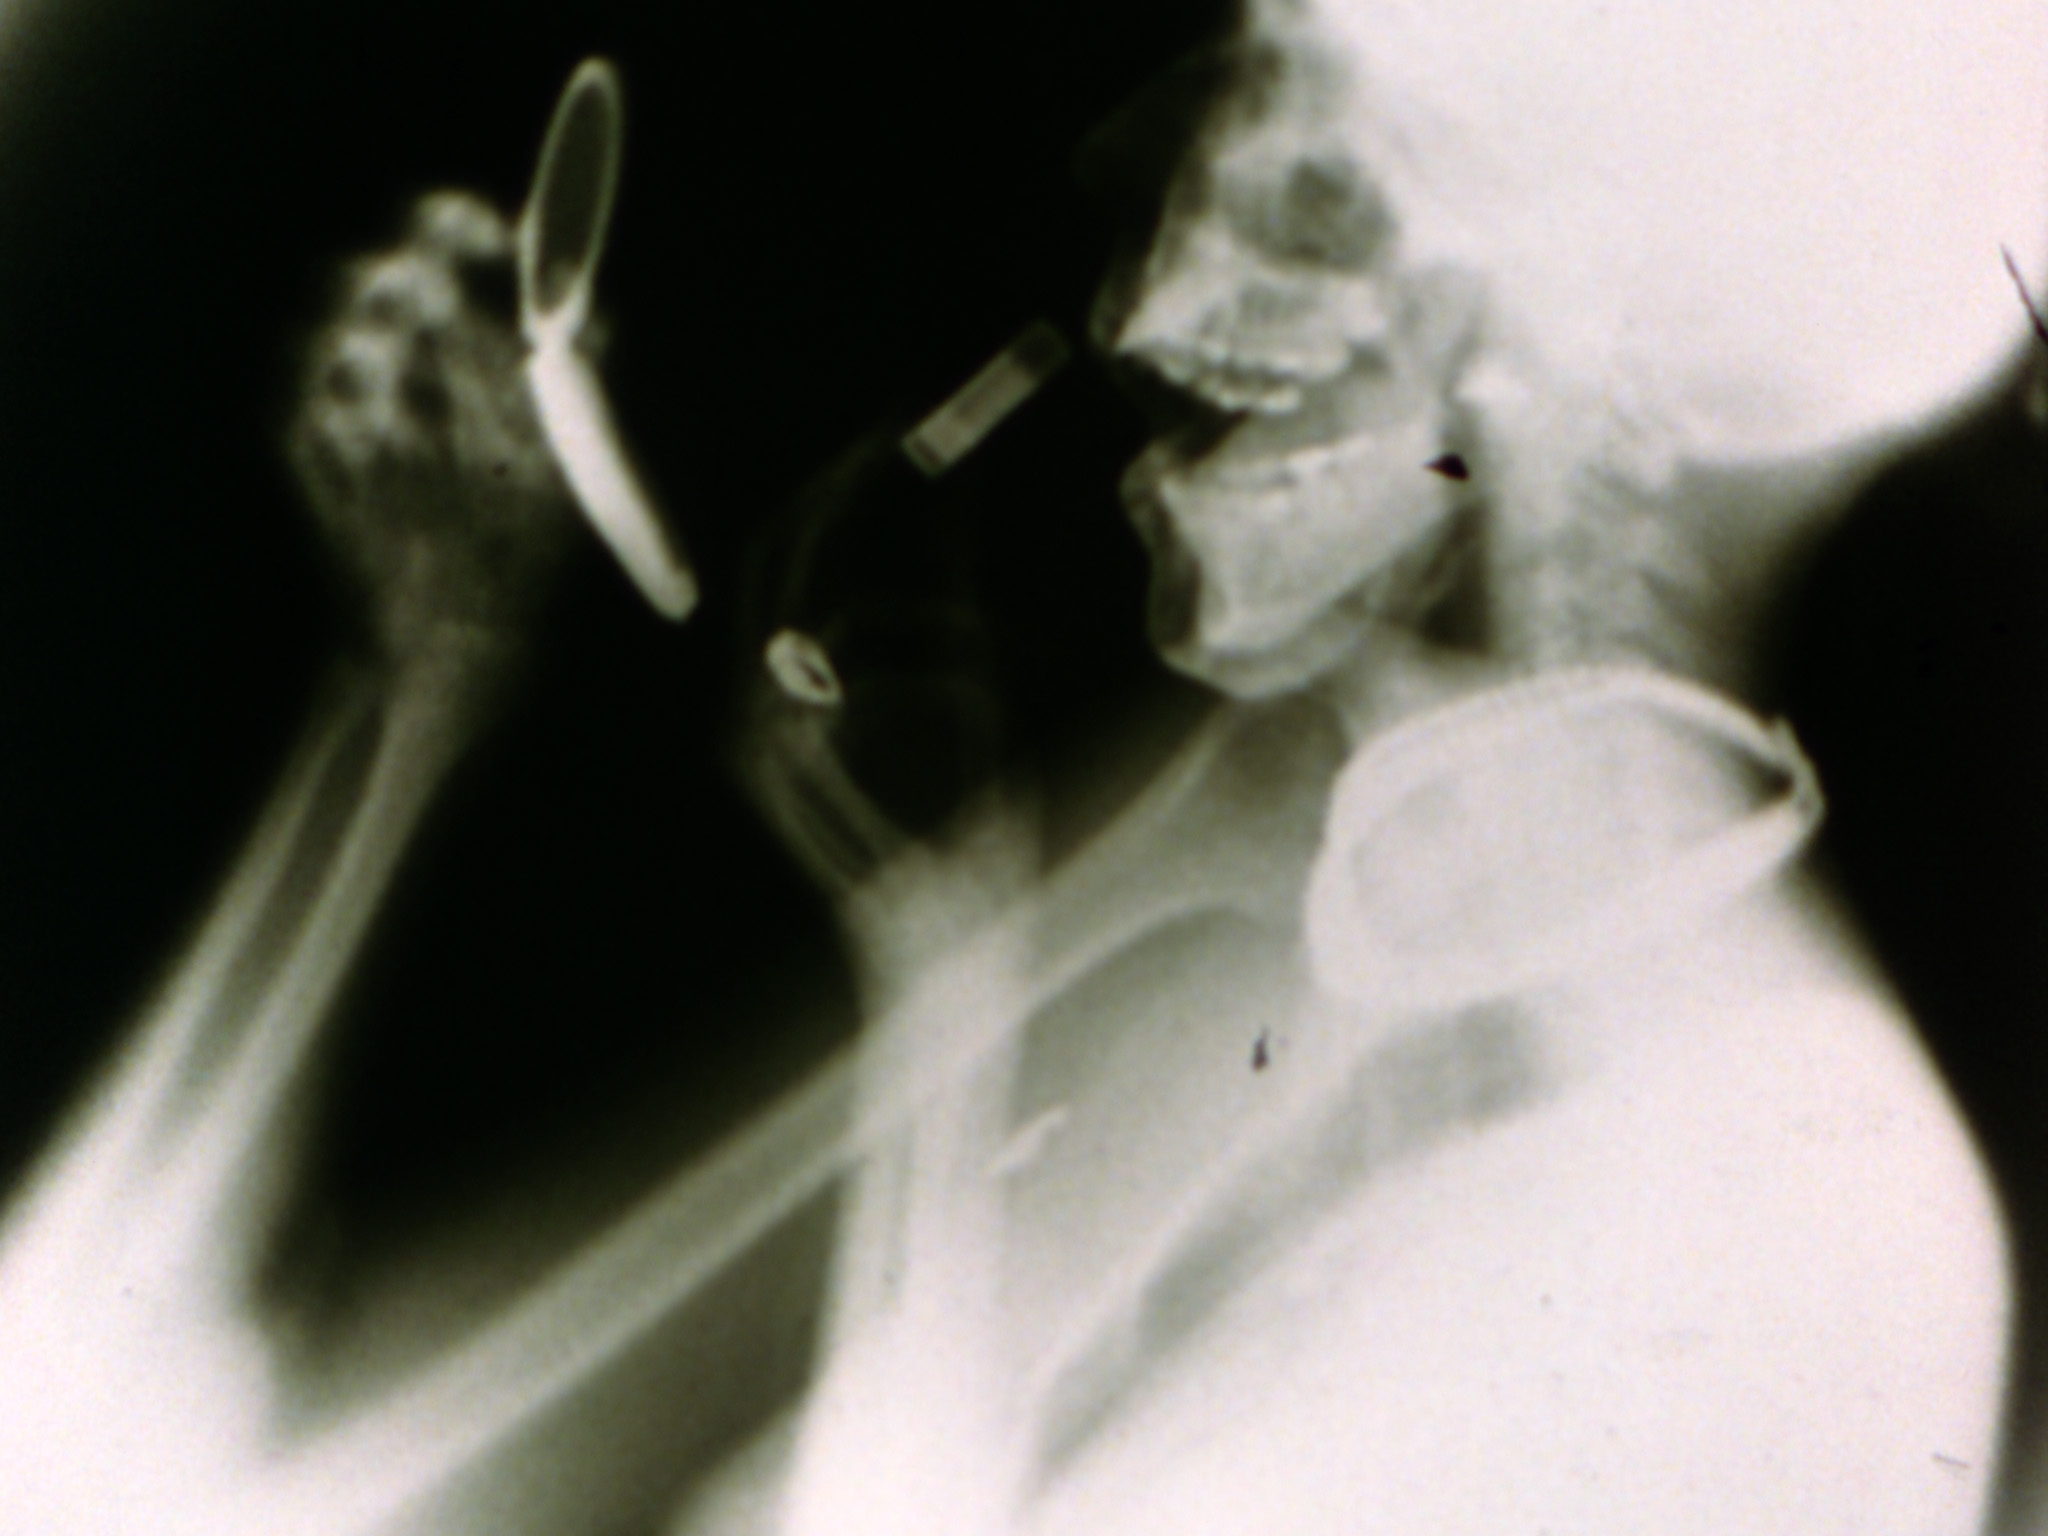

Sanctus is a film of rephotographed moving x-rays, originally shot by Dr. James Sibley Watson and his colleagues. Making the invisible visible, the film reveals the skeletal structure of the human body as it protects the hidden fragility of interior organ systems. Writes Hammer: "In making Sanct...